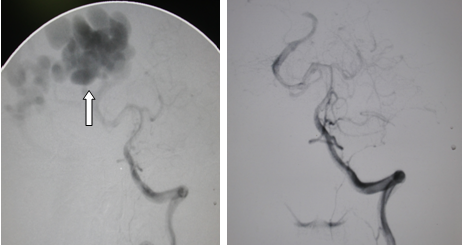

黄某,男性,41岁,因“头痛伴视物模糊20余天”入院,入院诊断:右颞枕叶AVM并出血,入院查全脑血管造影提示右枕叶巨大AVM,神经外科全体医师在手术前进行了深入地讨论,制定出详尽地手术计划,于2012-06-19全麻下行右枕叶巨大AVM切除术,术中见右枕叶有一团迂曲的血管团,大小6cm*5cm,血管团在横窦及小脑幕上形成高度扩张高流量静脉球,有一粗大的引流静脉与矢状窦及横窦相通,由右侧大脑后动脉供血,经过我院神经外科主任范学政博士、黄进能、王伯强等手术医师3小时显微手术,彻底切除右枕叶巨大AVM病变。术后病理提示“动静脉畸形”,术后复查全脑血管造影提示右枕叶巨大AVM已完全切除,术后患者头痛消失,视物较前清楚。于2012-07-04顺利出院。

箭头示右枕叶巨大动静脉畸形(AVM) 术后AVM消失